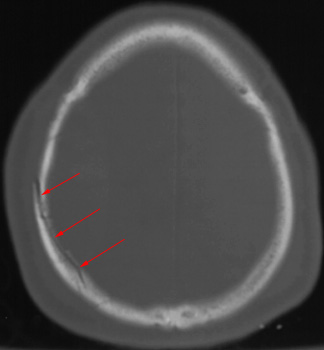

Head CT > Trauma > Skull Fracture

Skull Fracture

Skull fractures are categorized as linear or depressed, depending on whether the fracture fragments are depressed below the surface of the skull. Linear fractures are more common. The bone windows must be examined carefully. A skull fracture is most clinically significant if the paranasal sinus or skull base is involved. Fractures must be distinguished from sutures that occur in anatomical locations (sagittal, coronal, lambdoidal) and venous channels. Sutures have undulating margins both sutures and venous channels have sclerotic margins. Venous channels have undulating sides. Depressed fractures are characterized by inward displacement of fracture fragments.